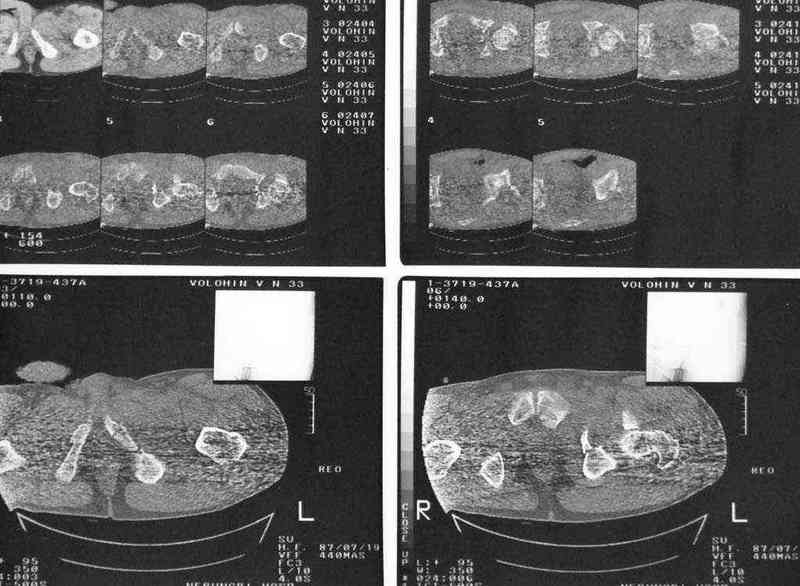

Для определения тактики лечения необходимы проекции фас, inlet и Judet

Дополнение, минимальный набор необходимых прекций, необходимых для лечения повреждений вертлужной впадины

Фас. Inlet

Подвздошная Запирательная

еще одно дополнение